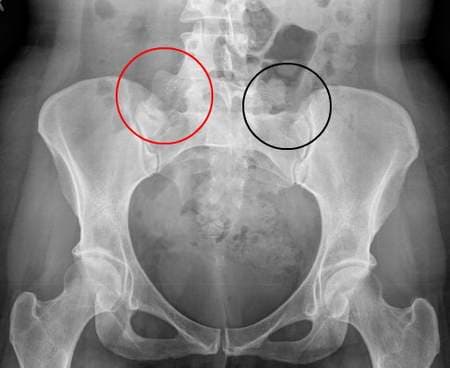

Người bệnh bị viêm khớp cùng chậu thường đau âm ỉ, kéo dài ở vùng cột sống thắt lưng cùng, giữa hai mông và vùng chậu hông khiến khả năng vận động dần bị hạn chế. Chữa viêm khớp cùng chậu ở đâu tốt, uy tín là mối quan tâm hàng đầu của những người bệnh.